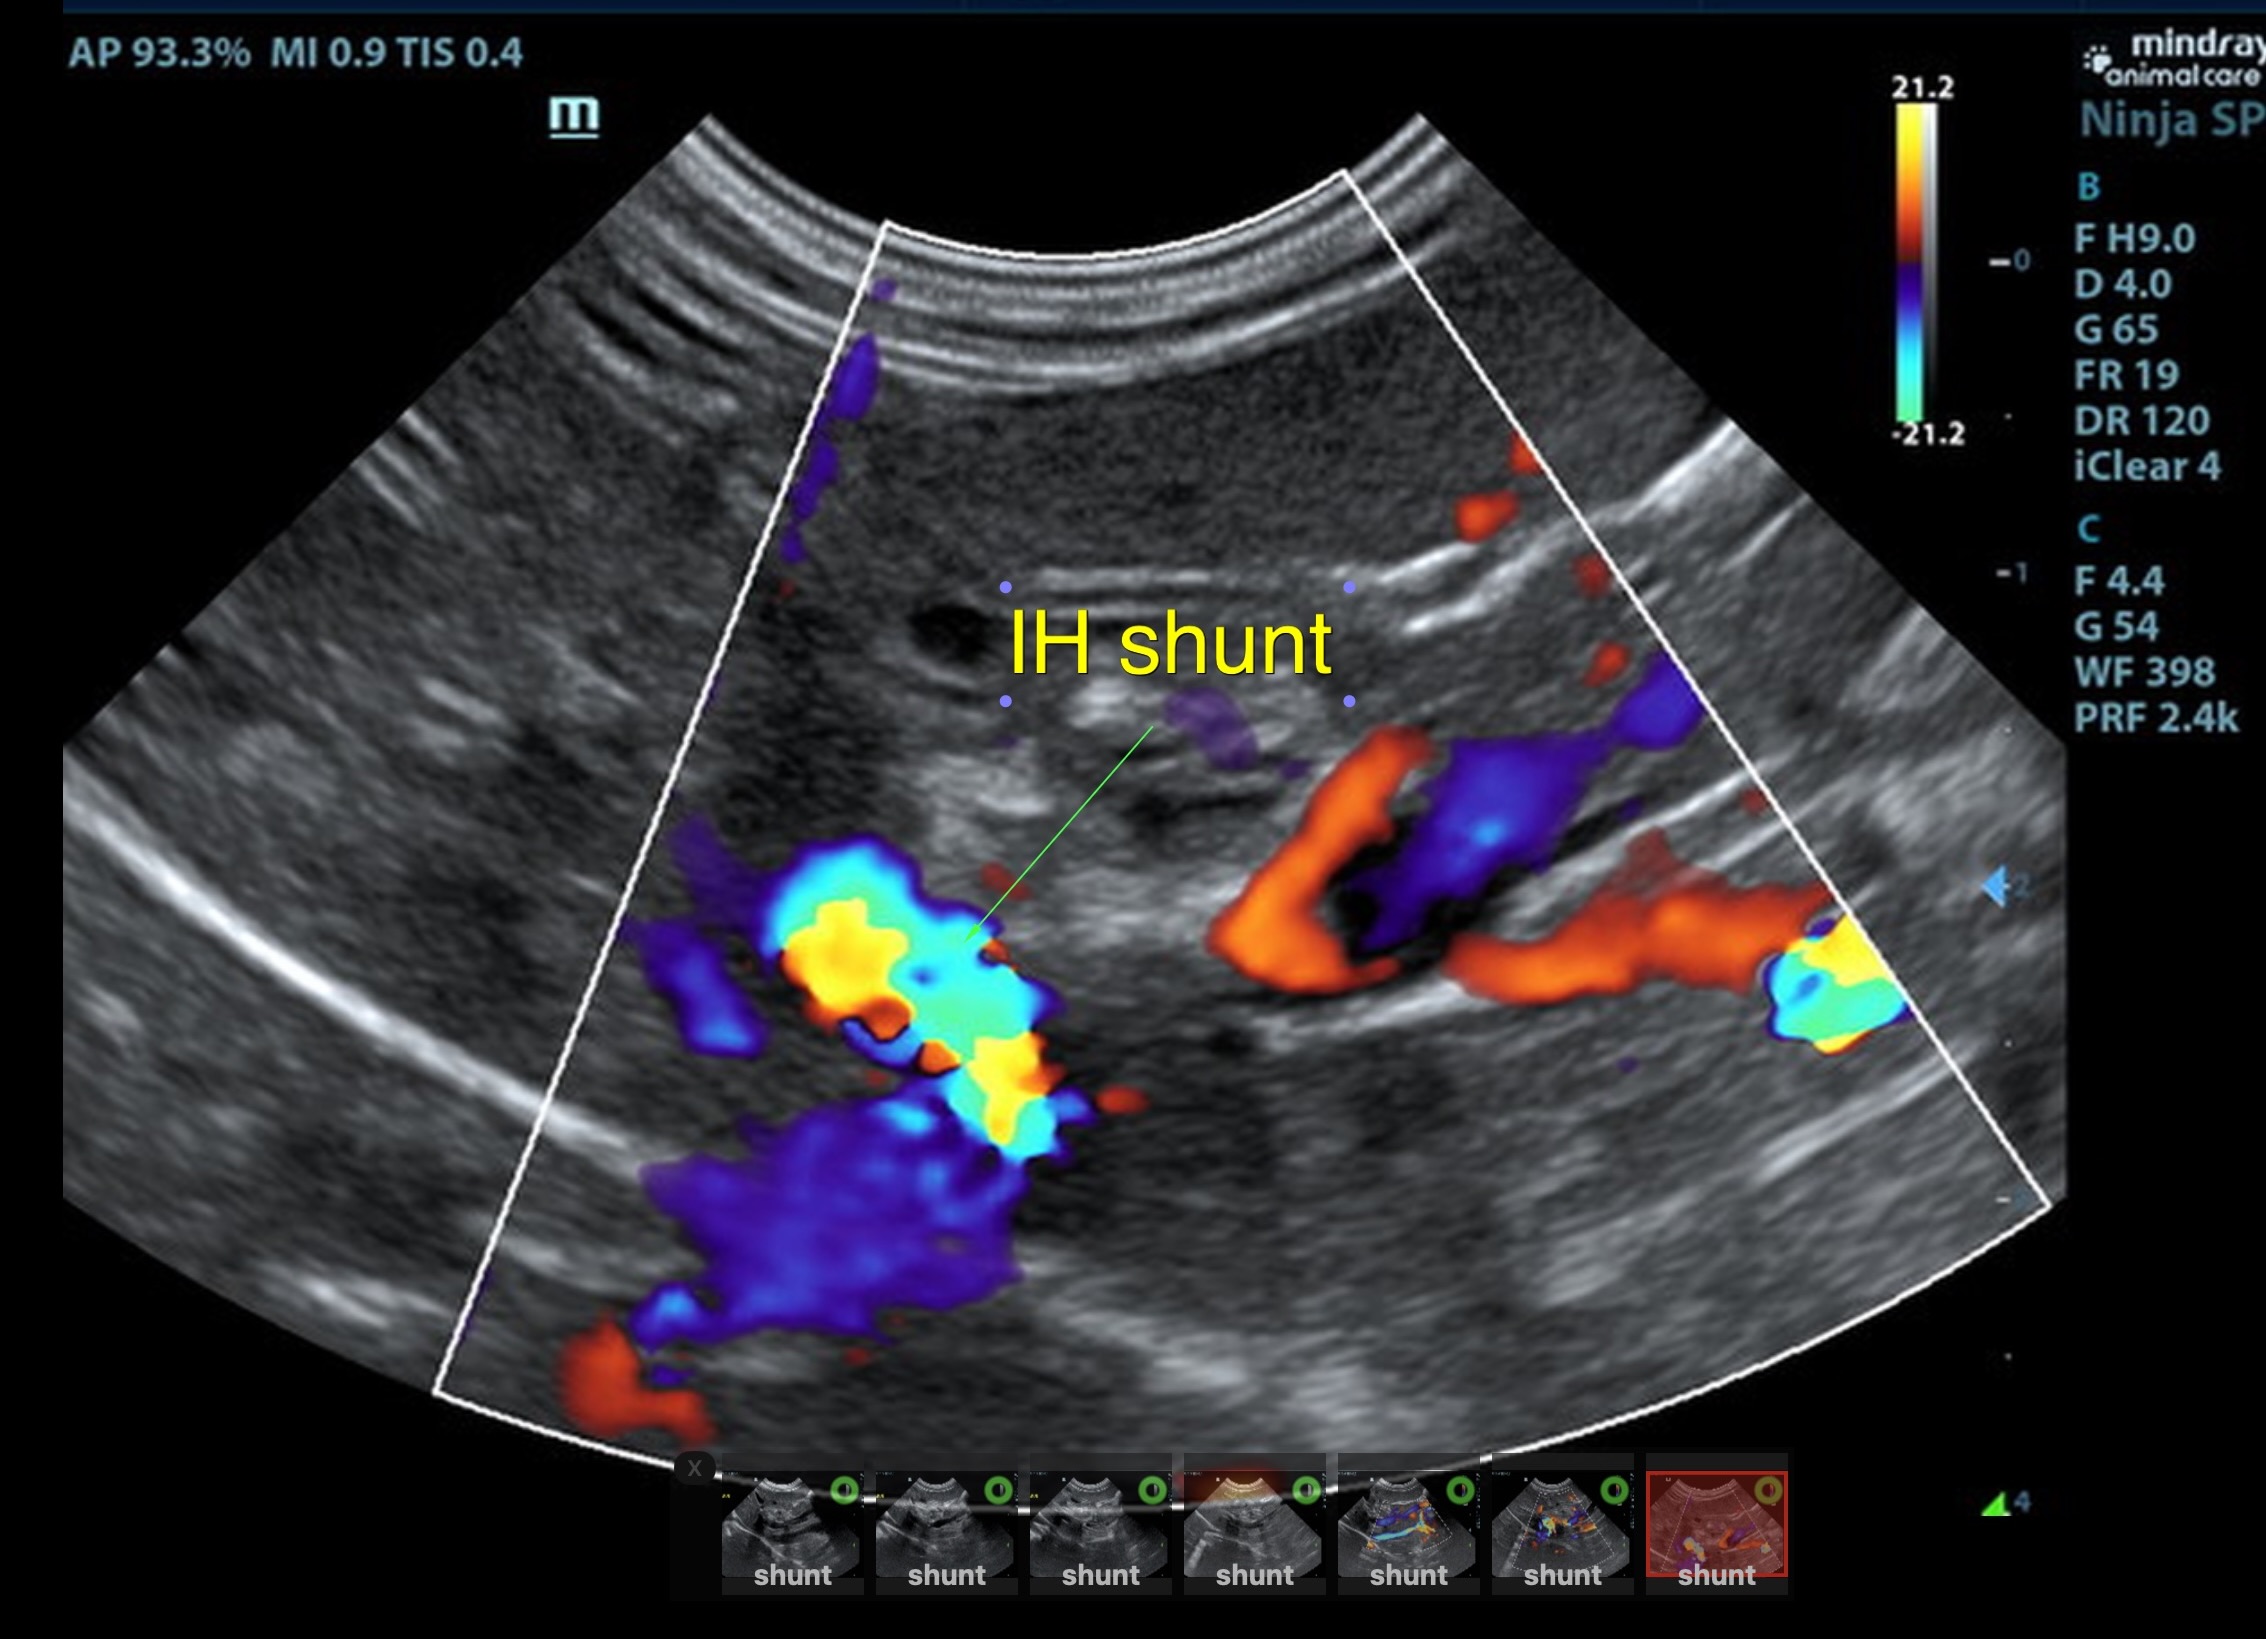

Suspect intrahepatic shunt, central divisional or right divisional.

The liver was subnormal in size, yet the portal vein and vena cava ratio was 1:1. The portal veins were subnormal in size and measured 0.34 cm. The vena cava was enlarged and measured 0.34 cm. The vena cava was enlarged and measured 0.72 cm, aorta measured 0.4 cm. The branching of the portal vein appeared to be normal and of adequate volume. The portal vein and vena cava measured 0.5 cm each in the extrahepatic space. The splenic vein entry into the portal vein and gastroduodenal vein entry into the portal vein appear to be normal. There was one turbulent vessel in the region of the central branch of the portal vein, which may represent an intrahepatic shunt, but this could not be confirmed. The width of the shunt is approximately 0.76 cm. This is in position of central divisional shunt; however, right divisional origin cannot be completely ruled out. The gallbladder presented acceptably thin walls with primarily anechoic content. The cystic and common bile ducts were normal.